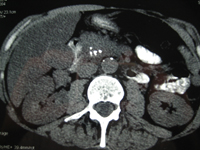

Calcifications dans le pancréas. Pancréatite chronique